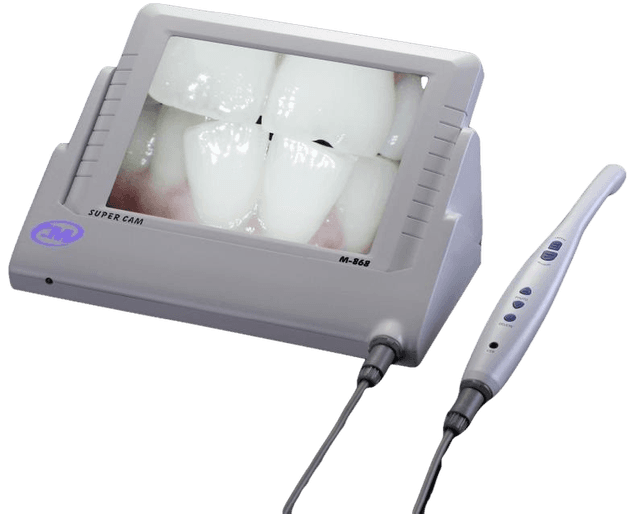

Новейший 3D-сканер для полного обследования